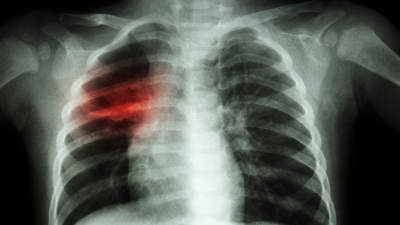

İnfluenza B salgını nedeniyle küçük büyük herkesin şu an hasta olduğunu söyleyen Çocuk Sağlığı ve Hastalıkları Uzmanı Dr. Şirin Seçkin, "Bu ara influenza B salgını söz konusu. İnfluenza B tedavi edilmezse yüzde 10 oranında akciğer enfeksiyonu (zatürre) oluşturabilir" dedi.

İnfluenza B'nin tedavi edilmezse yüzde 10 oranında akciğer enfeksiyonu oluşturabileceğini kaydeden Seçkin, "Yüksek ateş, öksürük, boğaz ağrısı belirtilerini gösterir. Yüksek ateşi olan çocuk bayılırsa, burun-diş eti kanaması olursa, kas ağrısı nedeniyle basamama, yürüyememe olursa muhakkak influenza bakılmalıdır, mutlaka doktora götürülmelidir. Çocuklarda kusma, ishal, sindirim sistemi şikayetleri daha ön plandadır" dedi.